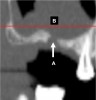

Fig 24. Turbinate bones: cross-sectional view. They are found within the nose. There is an inferior (A), middle (B), and superior turbinate (C).

Figure 24